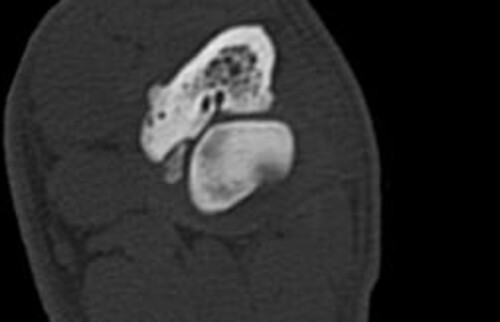

Nach der klinischen Diagnose werden die Hunde in unserer Klinik direkt im Computertomografen untersucht, sodass genau beurteilt werden kann, welche Gelenksanteile wie schwer betroffen sind, um eine individuelle Therapie festzulegen.

Schwarz-weiss Röntgenaufnahme